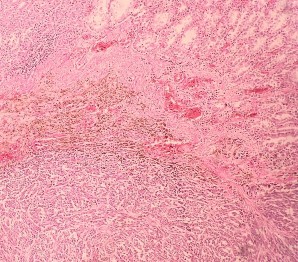

(Bệnh nhân : Hoàng Đình T.)

HE x 100: Tế bào u hình thoi, nhân lớn, rõ hạt nhân | HE x 400: U giàu nhân chia, bài tương giàu hạt sắc tố |

HE x 400: U giàu nhân chia, bài tương giàu hạt sắc tố | CHE x 400: U xâm nhập mạch bạch huyết |